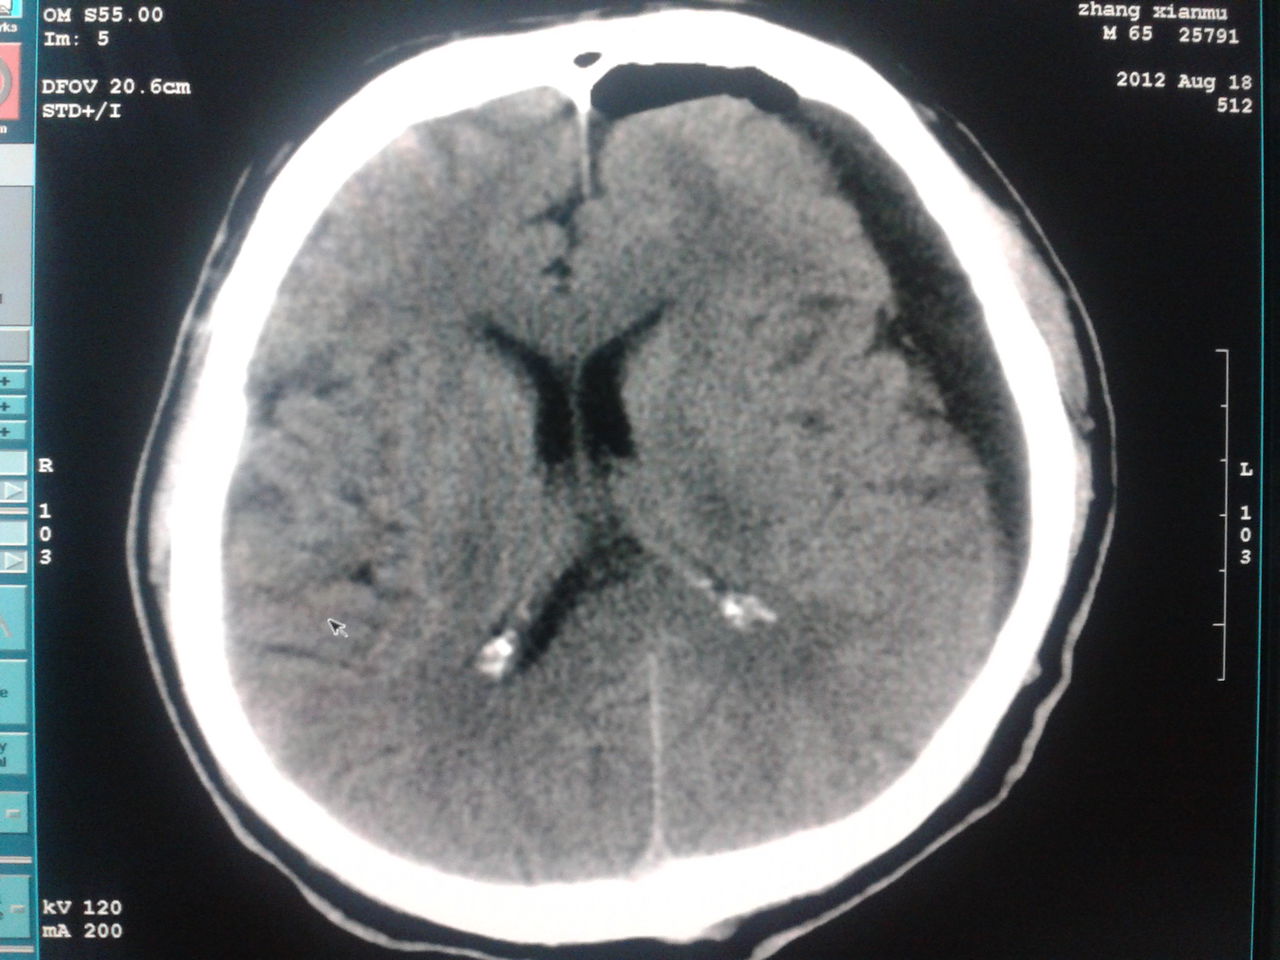

颅脑ct提示:双侧额颞顶部硬膜下积液,全科讨论后建议行腰椎诊断性穿刺

弥漫性轴索损伤合并双侧硬膜下积液案例